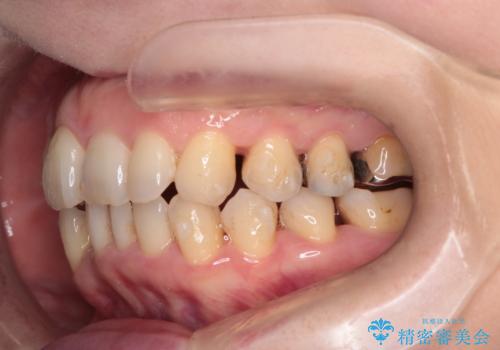

- 右上の八重歯(犬歯の突出)と、それに伴う歯並びのがたつきを主訴にご来院されました。精密検査の結果、八重歯を正しい位置に収めるためのスペースが大幅に不足していることが分かりました。

通常、矯正治療では4番目の歯を抜歯することが多いですが、今回は歯の状態や全体の噛み合わせのバランスを考慮し、右上5番(第二小臼歯)を抜歯してスペースを確保する計画を立案。装置には、周囲に気づかれずに治療を進めたいというご希望に合わせて、透明なマウスピース型のインビザラインを採用しました。

今回の治療では、右上5番の抜歯スペースを活用して八重歯(3番)を後方へ誘導しました。